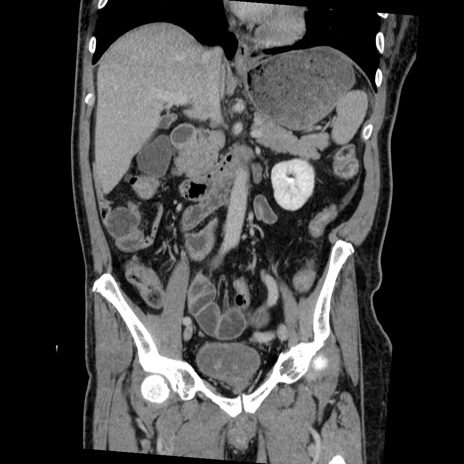

症例22(冠状断像)

【症例】50歳代男性

【主訴】腹痛

【現病歴】AVMからの被殻出血のため回復期リハ病棟入院中。 本日午後3時頃急に下腹部痛が出現した。

【既往歴】AVM、被殻出血、虫垂炎、高血圧

【身体所見】意識晴明、左半身不全麻痺、会話の理解は良好、36.5°C、腹部:膨隆、全体に板状硬、下腹部正中に圧痛点あり、反跳痛-、筋性防御不明、右下腹部にope scar

【データ】WBC 9400、CRP 0.06